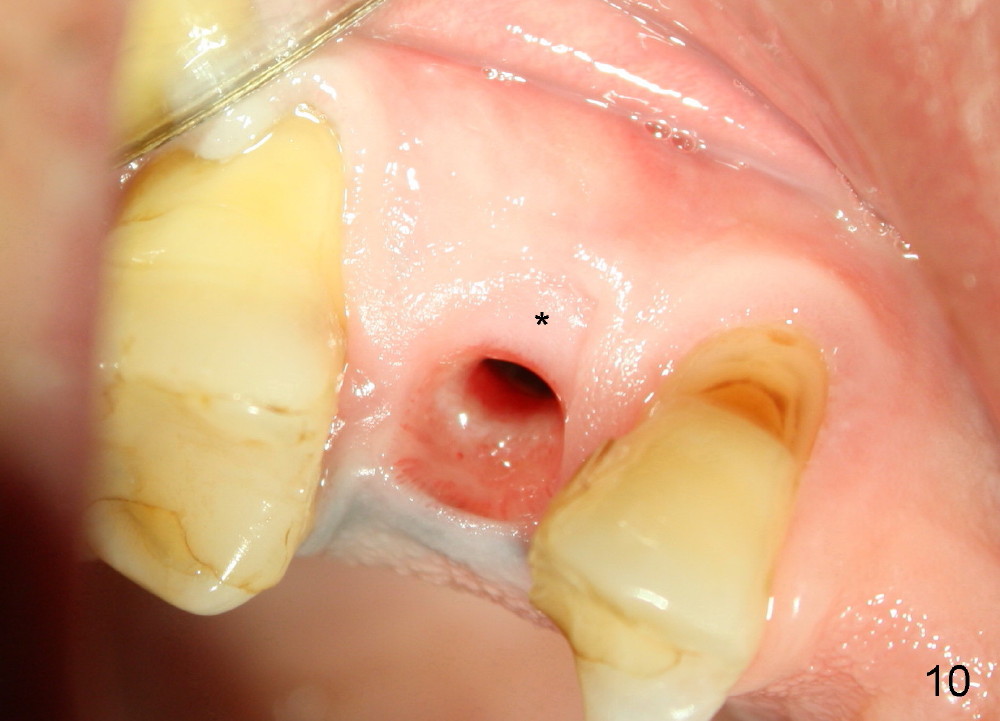

Due to insurance termination, restoration has to be done 2 months post implantation. Both the soft (Fig.10 *) and hard (Fig.11) tissues heal normally. A cemented abutment is placed (Fig.12 A). Fig.13 is taken 5 months post cementation. There is no bone resorption.